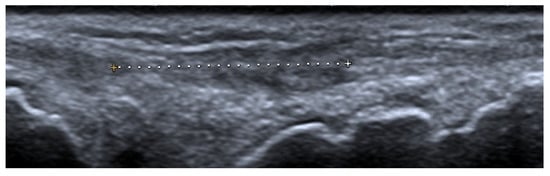

US may assist with the diagnosis and characterization of disease activity in inflammatory myopathies, with reported 82.9% sensitivity for detecting histologically proven myositis []. Inflammation and edema cause patchy or diffusely increased echogenicity of muscles, which may also appear swollen [,]. Increased vascularity on power Doppler may be seen []. In chronic diseases, the muscles appear atrophic with reduced volume and further increased echogenicity due to the progressive infiltration of fatty tissue [,,]. In addition, by shear-wave elastography (SWE), US is able to evaluate muscle stiffness []. Di Matteo et al. [] performed SWE on the quadriceps muscles in 30 SLE patients (without previous/current myositis or neuromuscular disorders) as well as 15 healthy subjects that matched the patients in age, sex, and BMI. SWE was significantly lower in SLE patients compared with the healthy subjects (1.5 m/s vs. 1.6 m/s respectively, p = 0.01).

Imaging modalities used in the assessment of osteoporosis include conventional radiography, conventional computer tomography (CT), dual-energy X-ray absorptiometry (DXA), quantitative CT, quantitative US, and MRI []. Today, radiography and DXA are the techniques of choice for vertebral fracture identification, whereas CT and MRI are used for characterization (dating and differential diagnosis) [] (Figure 11).